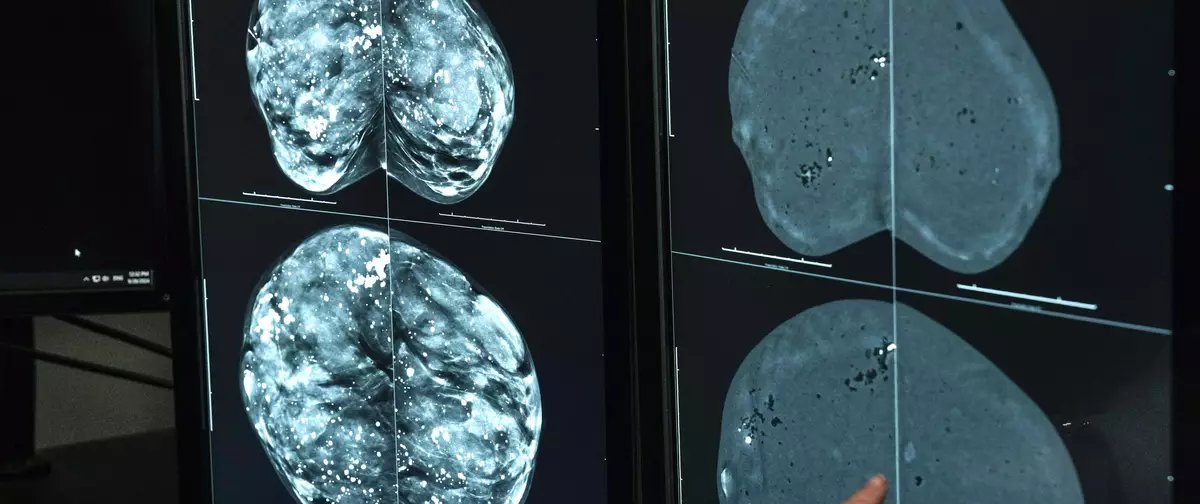

O câncer de mama é o tipo mais incidente e o que mais mata mulheres no Brasil, com cerca de 37 mil casos registrados anualmente. Somente em 2024, o Sistema Único de Saúde (SUS) efetuou aproximadamente 4 milhões de mamografias, exame considerado o principal método de rastreamento da enfermidade.